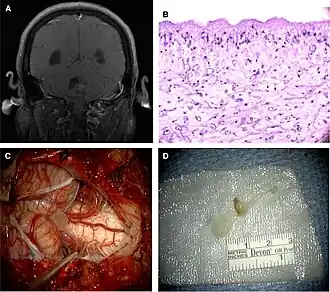

Neuroimaging

CT scans and magnetic resonance imaging (MRI) give objective information about the number and pattern of lesions, the stage of healing, and how the immune system is responding to the parasites.[19] MRIs are better for evaluating different spatial planes and provides clearer images, which helps in identifying small lesions at the back of the brain or near the skull that may be missed on CT scans. CT scans are more sensitive at detecting calcium buildup in the brain due to its ability detect calcifications in the brain.[30]

Live vesicular cysts are small, round lesions with little swelling around them and do not need contrast for imaging. The tapeworm head (scolex) usually appears as an asymmetric nodule inside the cysts. Multiple live cysts with these heads corroborate the diagnosis. Once the cysts begin to break down (colloid cysts), their borders become unclear, they are surrounded by swelling and exhibit significant ring or nodular contrast enhancement. Calcified cysticerci are shown on CT scans as non-enhancing hyperdense nodules without swelling.[20]

- Confirmation of the parasite through tissue analysis from a biopsy of a brain or spinal cord lesion.